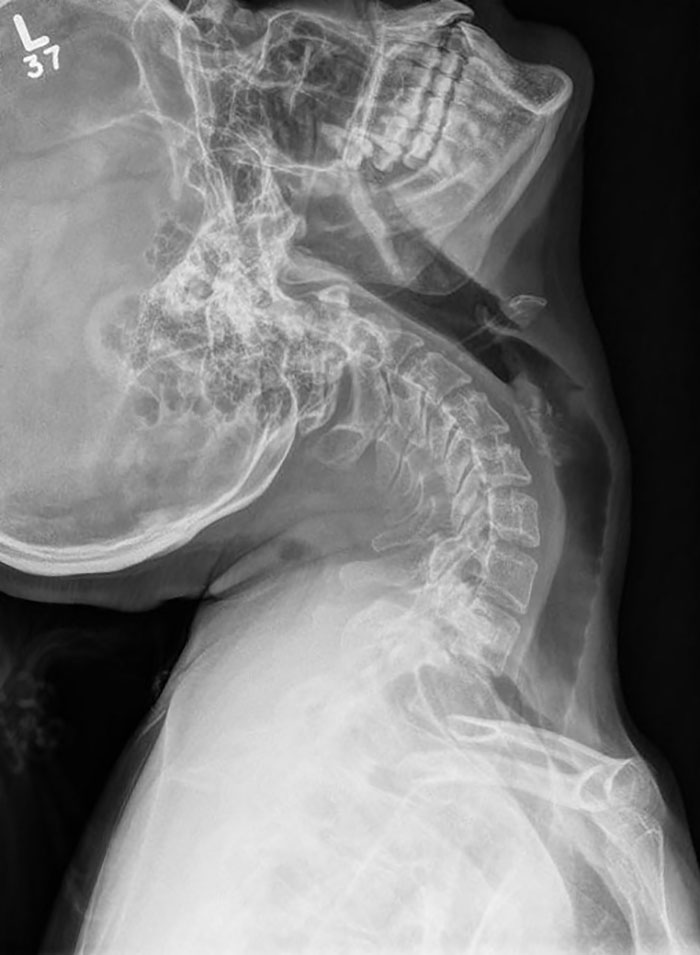

X-Ray Techs Were Amazed At My Cervical Spine Imaging Given Extreme Hyper Mobility